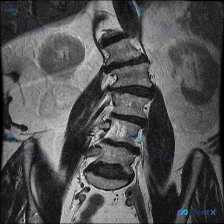

整理到一份影像资料,有点意思: 只有腰椎MRI T1加权矢状位,能看到: 1. 腰椎生理前凸存在,但L5/S1有明显的腰椎滑脱(L5相对于S1向前移位) 2. 下腰椎多个椎间盘信号减低、L4/L5和L5/S1椎间隙变窄 3. 对应节段终板有Modic II型改变(脂肪化) 4. L4/L5及L5/S...

整理到一份腰椎冠状位MRI影像资料,先给大家看客观表现: - 脊柱力线:腰椎向右侧侧弯 - 椎体:高度、排列大致连续,无明显滑脱,骨质信号未见明确局灶异常 - 椎间盘:普遍T2低信号(脱水退变),下腰椎(L3/4-L5/S1)椎间隙变窄,冠状面见轻度周边膨隆 - 小关节:多节段骨质增生、间隙窄,呈退...

整理到一份有意思的影像读片资料: 本来是做腰椎及肾脏的MRI-T2冠状位,主要想看肾脏情况——结果肾脏看起来倒没明显占位、积水或结石,皮髓质分界也清;但腰椎这边,第一眼扫过去椎体排列好像有点不对劲? 原报告提了椎间盘信号略减低(考虑退变),但说“整体对称性良好”;后来重新看,有人明确指出冠状位上腰椎...